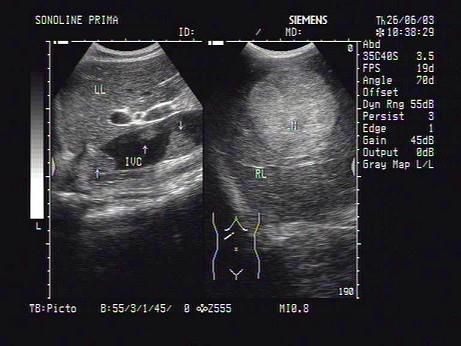

某患者肝脏声像图表现如图,诊断为?(?)A.肝海绵样血管瘤B.肝癌并布加综合征C.肝脓肿并血栓形成D.肝淤血E.肝硬化并门脉血栓形成

问题 某患者肝脏声像图表现如图,诊断为?(?)

选项 A.肝海绵样血管瘤 B.肝癌并布加综合征 C.肝脓肿并血栓形成 D.肝淤血 E.肝硬化并门脉血栓形成

答案 B